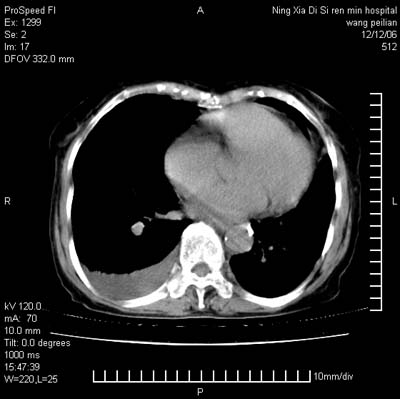

标题: CT5609:胸部:女77 病史不详 [打印本页]

标题: CT5609:胸部:女77 病史不详

两肺可见多个大小不等的结节,左侧有胸水,纵隔淋巴结增大,考虑是细支气管肺泡癌

两肺尖纤维索状影,两下肺结节块状影,且有钙化灶,右胸腔积液。考虑肺结核并胸膜炎。

两肺尖纤维索状影,两下肺结节块状影,且有钙化灶,右胸腔积液。考虑肺结核并胸膜炎肺间质纤维化

考虑:1、慢性支气管炎合并全小叶型肺气肿、间质纤维化;

2、双肺结核;

3、右侧胸膜炎(积液)。

1、双肺继发型肺结核(以纤维、增殖灶为主);

2、右侧胸腔积液;

3、其余符合老年肺改变。

双肺见多个结节状及条索状影,双侧胸腔积液,右侧叶间积液,考虑结核性胸膜炎